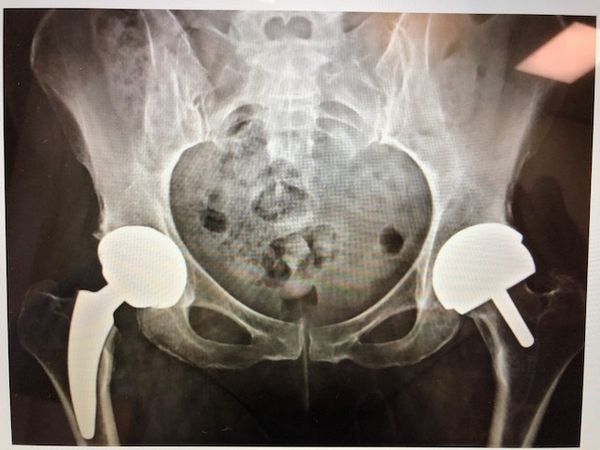

Коксартроз (артроз тазобедренного сустава)

Поэтапное хирургическое лечение коксартроза